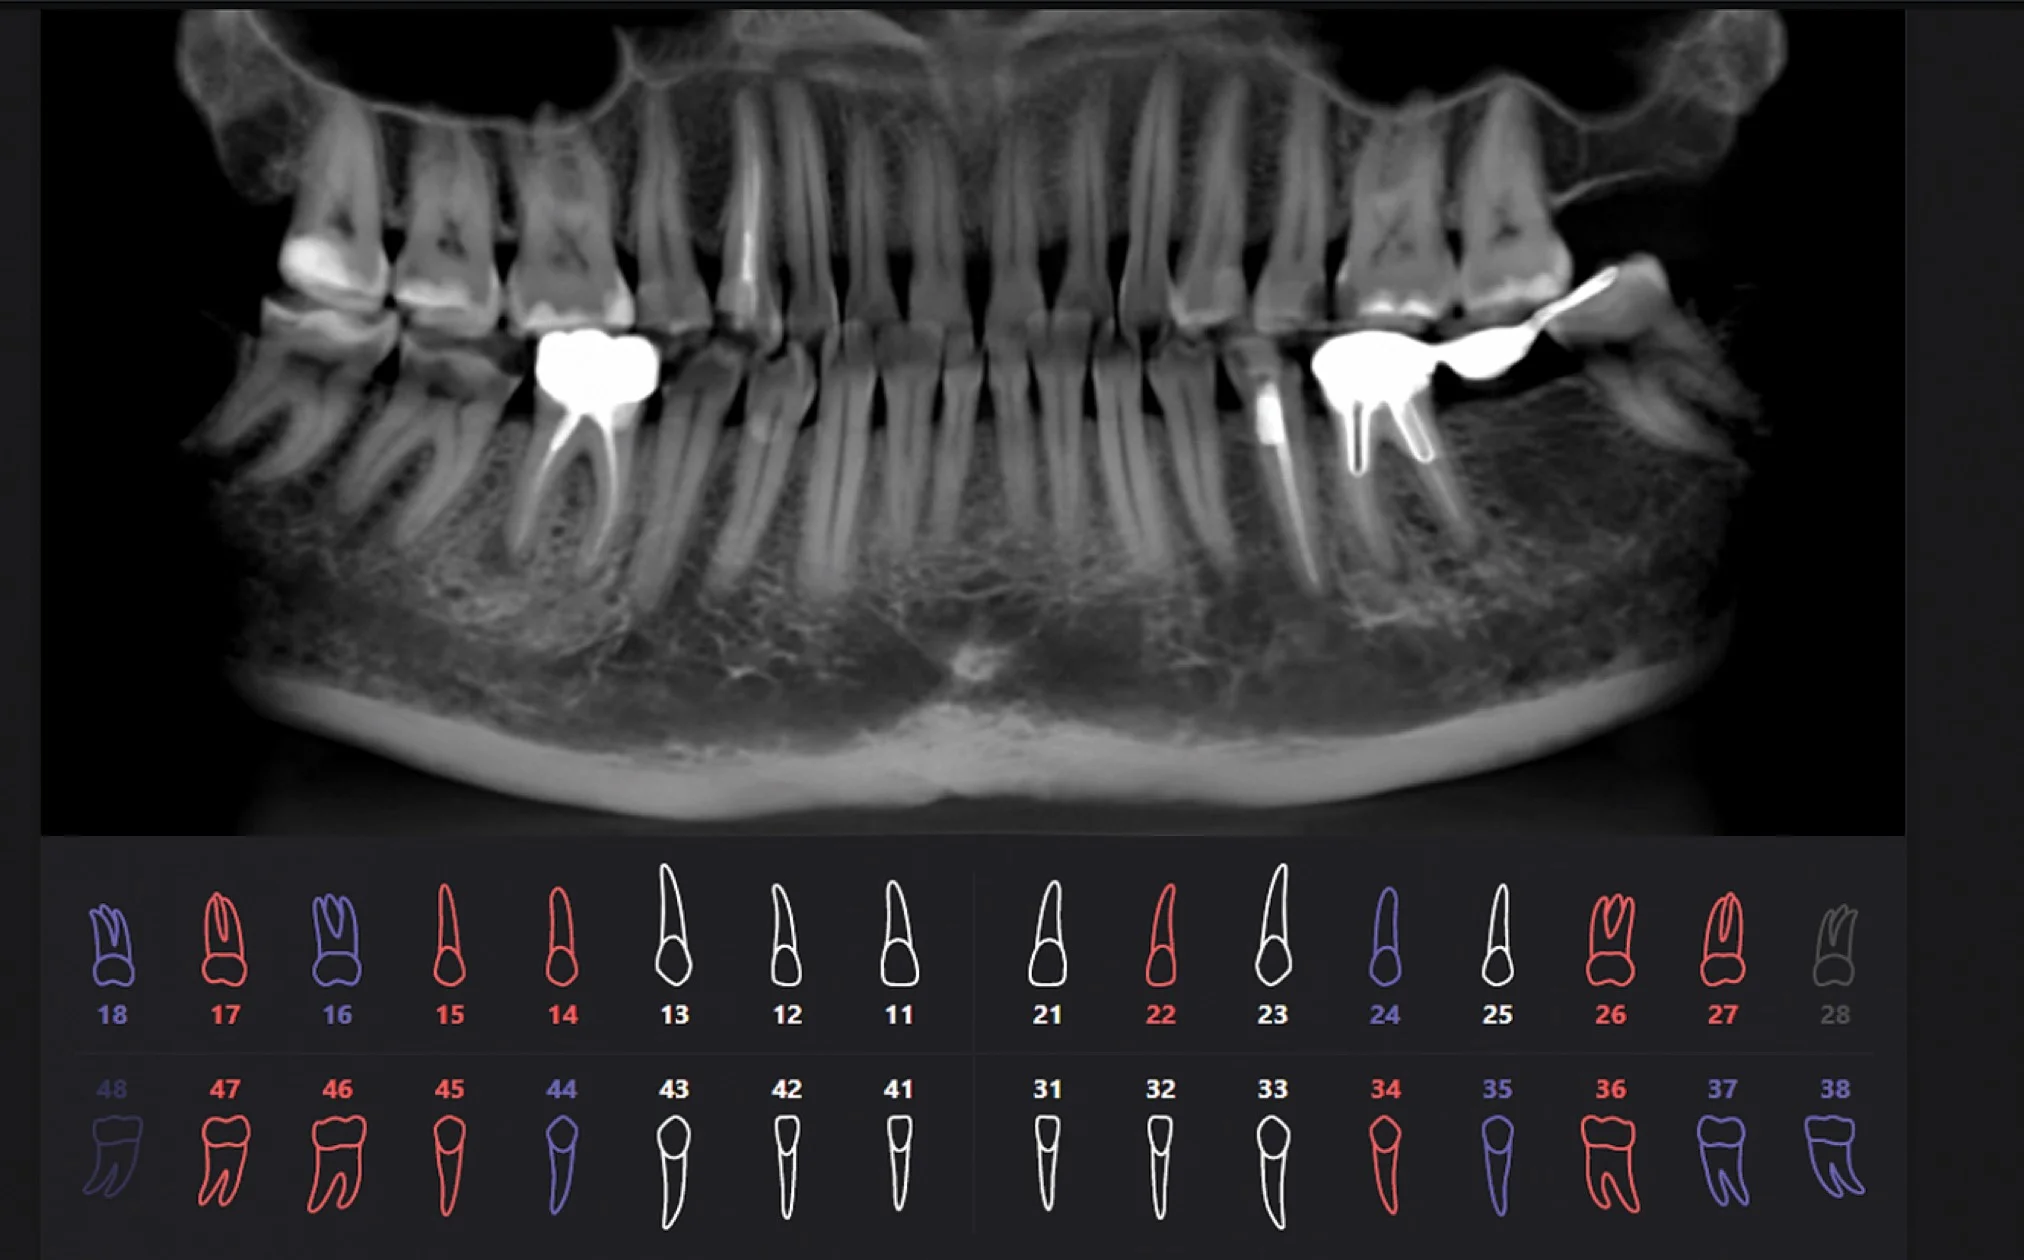

Для решения этих проблем была создана Российская разработка, работающая на основе искусственного интеллекта.

- Программа ежедневно собирает данные 3D снимков со всей России и совершенствуется в их чтении;

- На данный момент было изучено более 60 000 КТ снимков;

- Программа разрабатывается с участием ведущих мировых экспертов челюстно-лицевых рентгенологов и стоматологов.

Результат работы искусственного интеллекта

Красным цветом показаны проблемные зубы, синим цветом — зубы с пломбами или ортопедическими конструкциями, белым цветом — здоровые зубы.

Сравнение подходов в изучении 3D снимков

Когда мнение врача и искусственного интеллекта отличается

Мнение врача и искусственного интеллекта иногда может отличаться, это сигнал для того, чтобы более глубокого изучить проблемную область, назначить ремтерапию, динамическое наблюдение.

Определяющее мнение всегда остается за врачом.